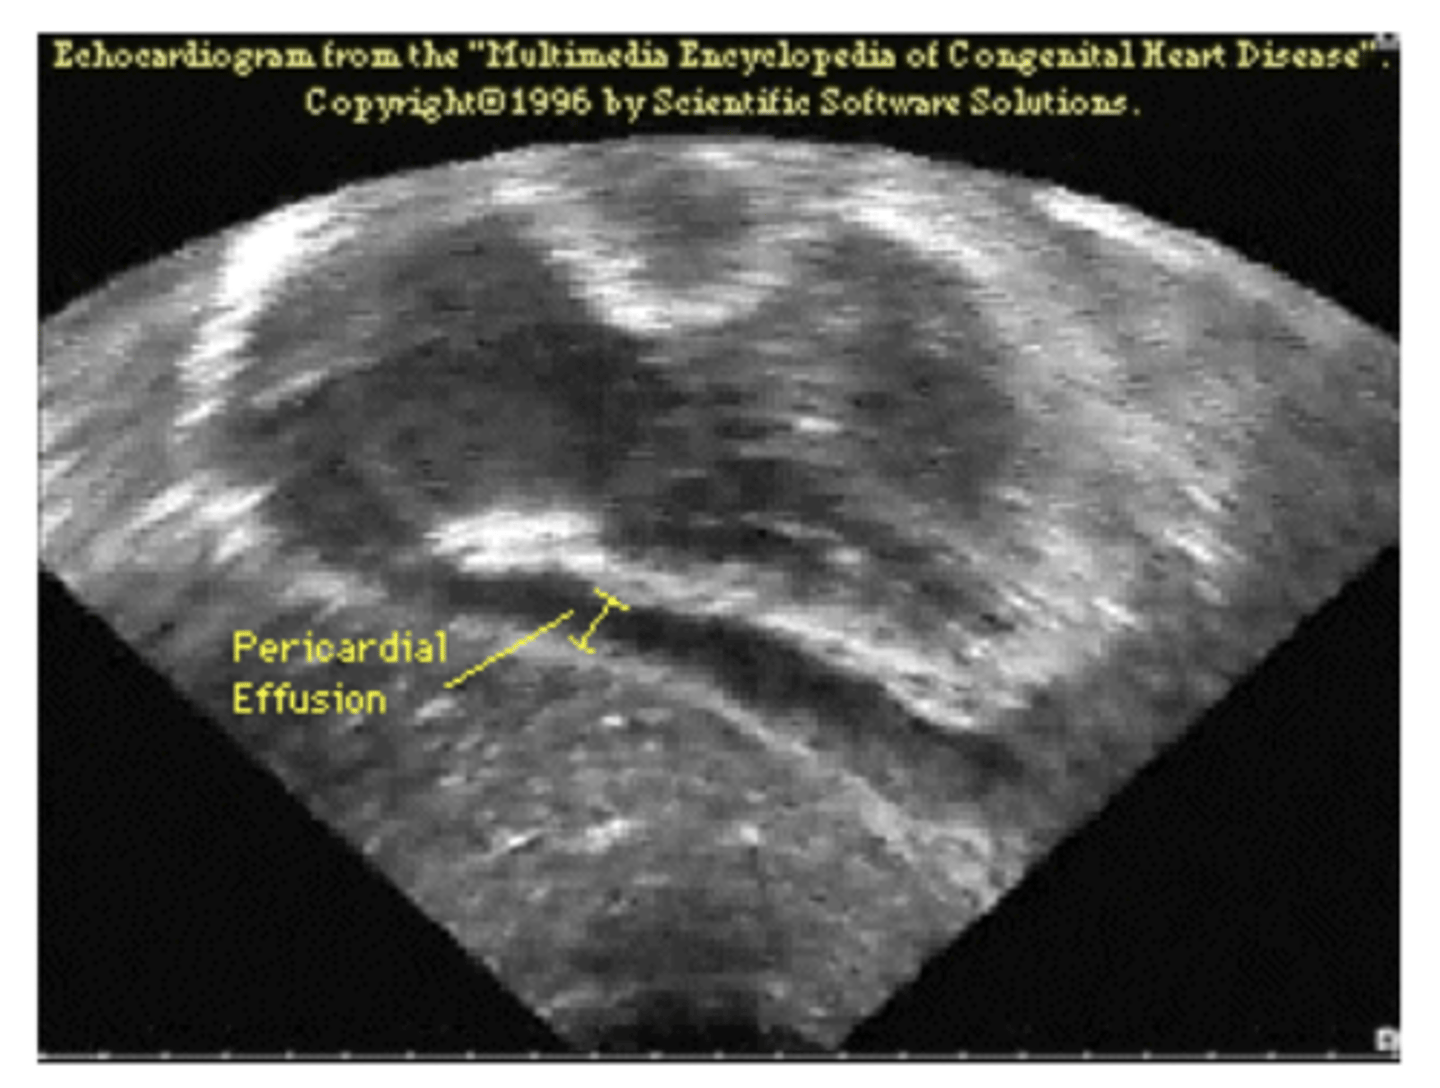

What is the typical appearance of pericardial effusion? Imaging of choice

Pericardial effusion causes an acute marked

enlargement with the heart appearing pendulous and very wide at the base – “water bag appearance.”

echocardiogram is imaging of choice (image here is x-ray)

<p>Pericardial effusion causes an acute marked</p><p>enlargement with the heart appearing pendulous and very wide at the base – “water bag appearance.”</p><p>echocardiogram is imaging of choice (image here is x-ray)</p>

What does epicardial effusion look like on ECG?

area of darkness around heart

<p>area of darkness around heart</p>